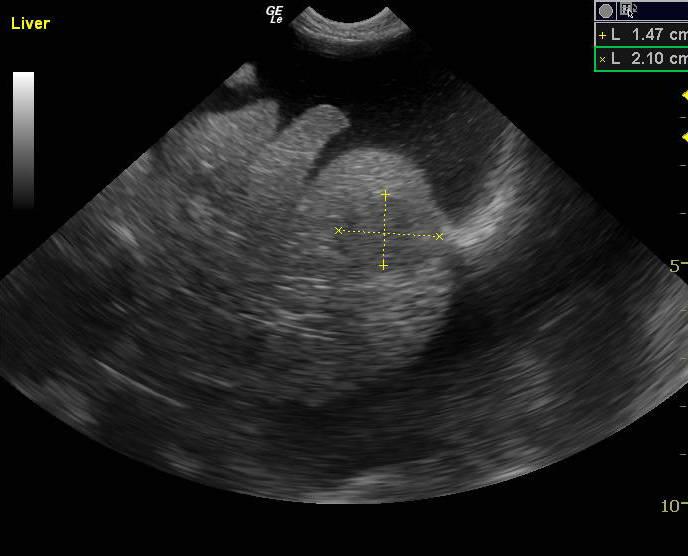

The abdomen in this patient presented moderate amount of echogenic free fluid. Multiple heterogenous nodular changes were noted which were hypoechoic and hyperechoic throughout the liver. This is suggestive for metastatic event. Some internal structure deviation was noted. The deep right liver revealed a collapsed gallbladder with surrounding parenchymal nodular changes with impingement upon the gallbladder. The vena cava was normal. The hepatic veins were subnormal in size. This is indicative of an increased possibility of feline infectious peritonitis. The pancreatic region revealed multiple nodular hypoechoic changes with irregular surrounding omentum.

Pancreas: carcinoma. Liver: carcinoma (suspected metastatic).

FNA of liver revealed carcinoma (suspected metastatic). FNA of pancreas: carcinoma. Comments: Given the appearance of the slides as well as the sonographic description, the pancreas is likely the site of primary neoplasia, with metastases to the liver. The neoplastic cells appear epithelial but do not contain zymogen granules typical of normal pancreatic cells. This could be because the cells are sufficiently anaplastic as to have lost this feature, but other sources should be considered as well.